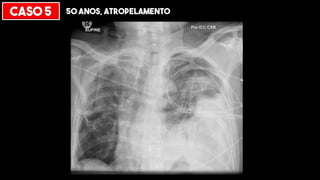

CASO 5 50 ANOS, ATROPELAMENTO

RUPTURA DIAFRAGMÁTICA